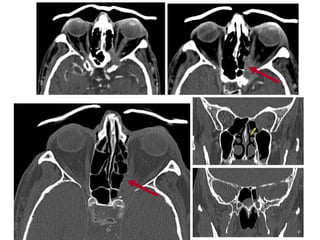

Zefalea eta begi paralisia kasu klinikoa PPTX

Zefalea eta begi paralisia kasu klinikoa (ii)